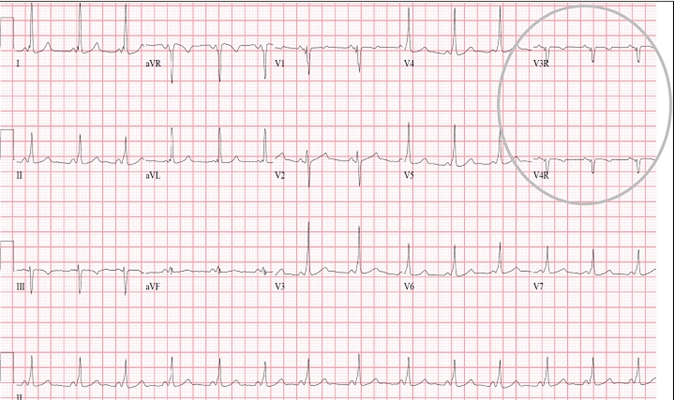

高鉀血癥心電圖 (43)

高鉀血癥心電圖 (44)

高鉀血癥心電圖 (45)

高鉀血癥心電圖 (46)

高鉀血癥心電圖 (47)

高鉀血癥心電圖 (48)

高鉀血癥心電圖 (49)

高鉀血癥心電圖 (5)

高鉀血癥心電圖 (50)

高鉀血癥心電圖 (51)

高鉀血癥心電圖 (52)

高鉀血癥心電圖 (53)

高鉀血癥心電圖 (54)

高鉀血癥心電圖 (55)

高鉀血癥心電圖 (56)

高鉀血癥心電圖 (57)

高鉀血癥心電圖 (58)

高鉀血癥心電圖 (59)

高鉀血癥心電圖 (6)

高鉀血癥心電圖 (7)